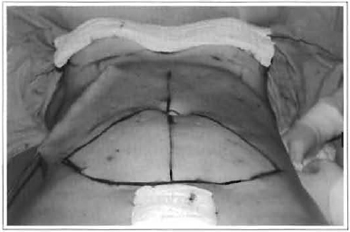

Fig. 5 - Marking the plicature.

Star-shaped omphaloplasty is performed, which consists of marking a "cross" on the abdominal skin.

The navel is then pulled out at its cardinal points with a forceps, and then small triangular resections are performed between these points, so that the navel fits into the cross-shaped incision on the skin, to be then fixed with subdermal sutures with Nylon 5-0.

For patients with indication for plicature of the rectus abdominis, divulsion or detachment of the subcutaneous tissue is performed over the median line, avoiding going beyond the internal borders of these muscles, thus preserving abdominal perforans vessels (Fig. 5). In the infra umbilical portion, the fat tissue is resected at the median line, and then conventional plicature of the aponeurosis is performed.